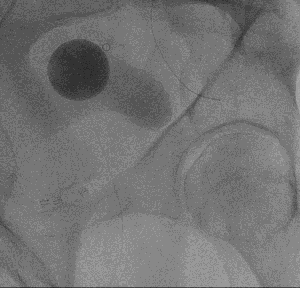

side-by-side fluoroscopic images showing pelvic vascular anatomy; the left panel displays a contrast-filled arterial tree with catheter in place, and the right panel shows a round radiopaque marker and surrounding bony structures during prostate artery embolization

picture 2Overall, the procedure involves shrinking the prostate by treating its blood vessels. An interventional radiologist gains access through a small incision in the upper thigh or the wrist. From there, small particles are injected into the prostate to slow the blood flow to the gland, causing the prostate to shrink. Relief from BPH symptoms occurs in the following weeks and months. It is a relatively painless procedure using conscious sedation. After the procedure, UCSF Radiology follows up with patients at one, six and 12 months.